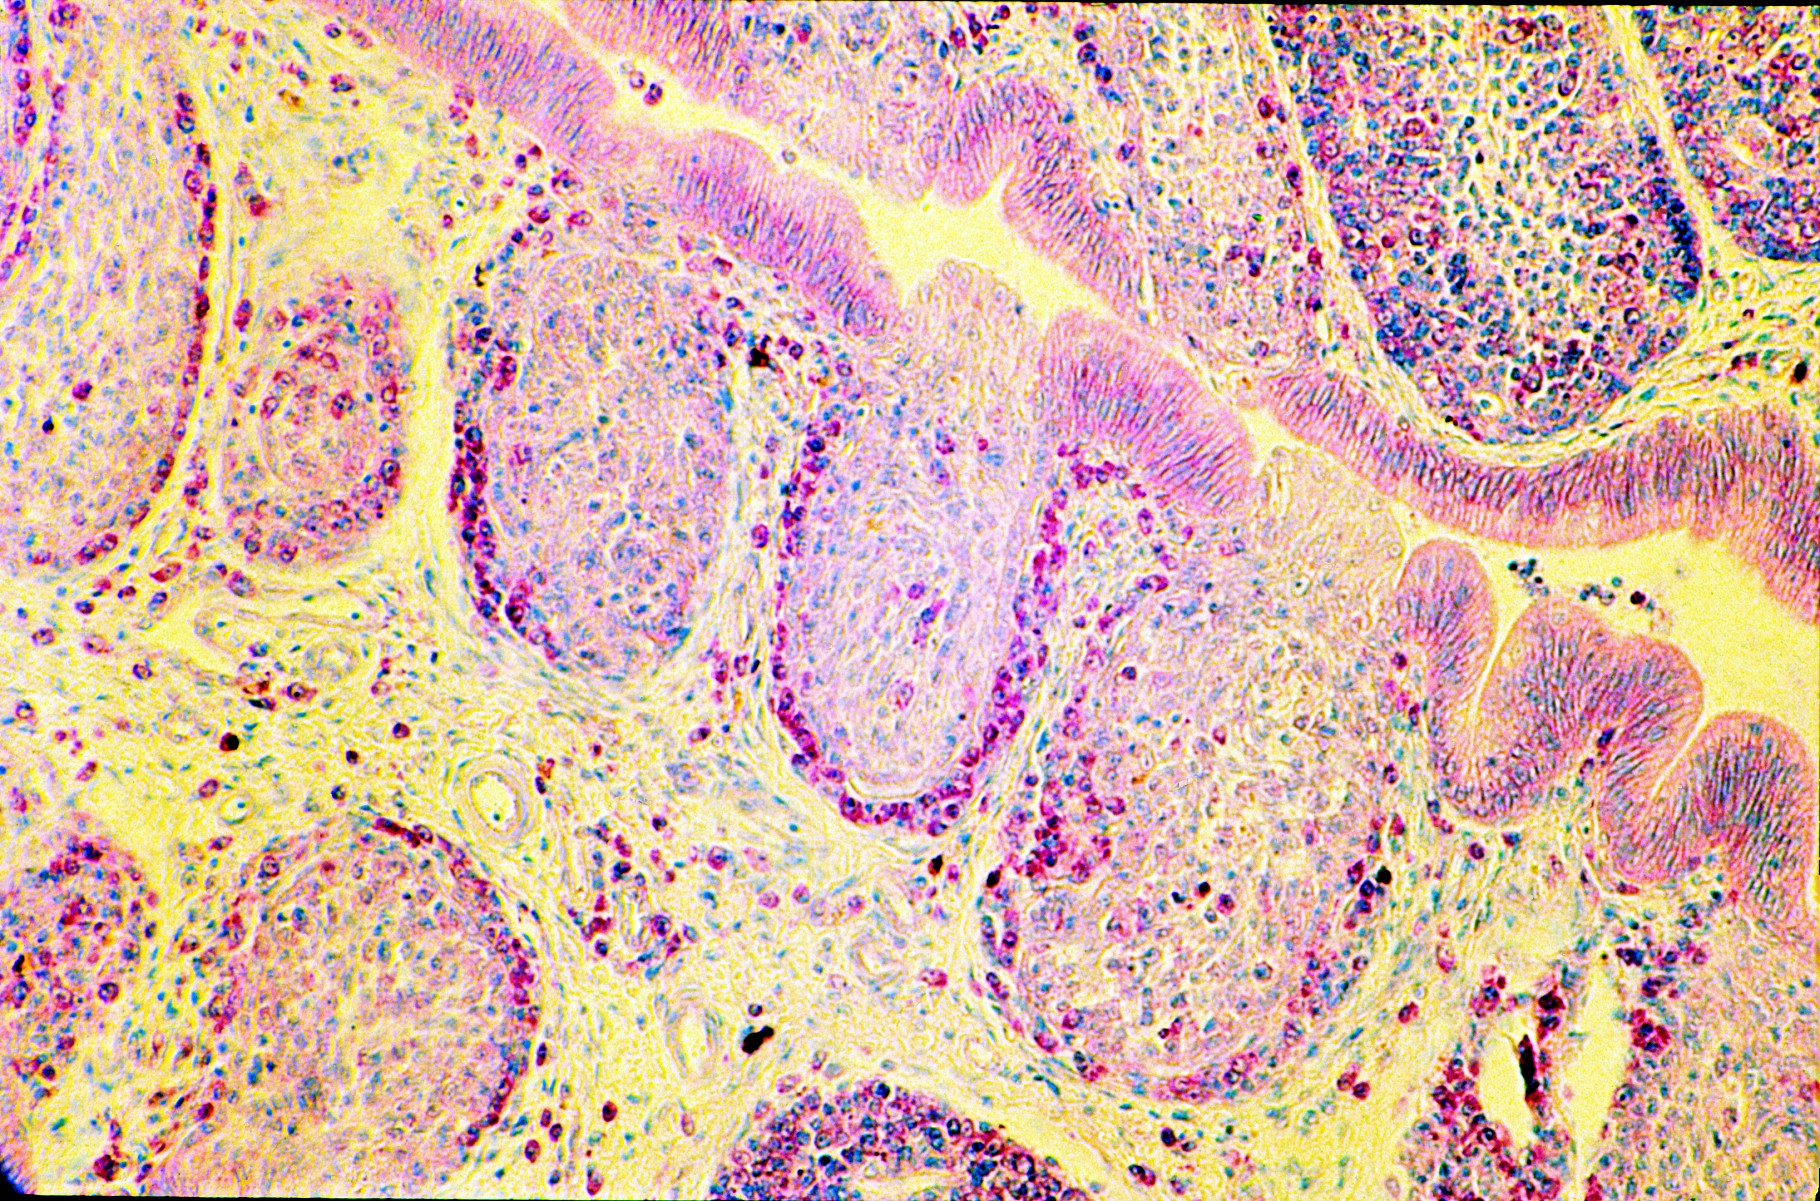

Image (37. Cy ablated bursa low power.)

37._Cy_depleted_follicles Available under License Creative Commons Attribution. Download (516kB) |

Reconstitution of cyclophosphamide depleted bursal follicles and effects of constitutive over expression of Myc and other transgenes in chickens. Images from “An atlas of normal and Myc-induced neoplastic development in the bursa of fabricius.” Access the full Atlas at http://authors.fhcrc.org/368